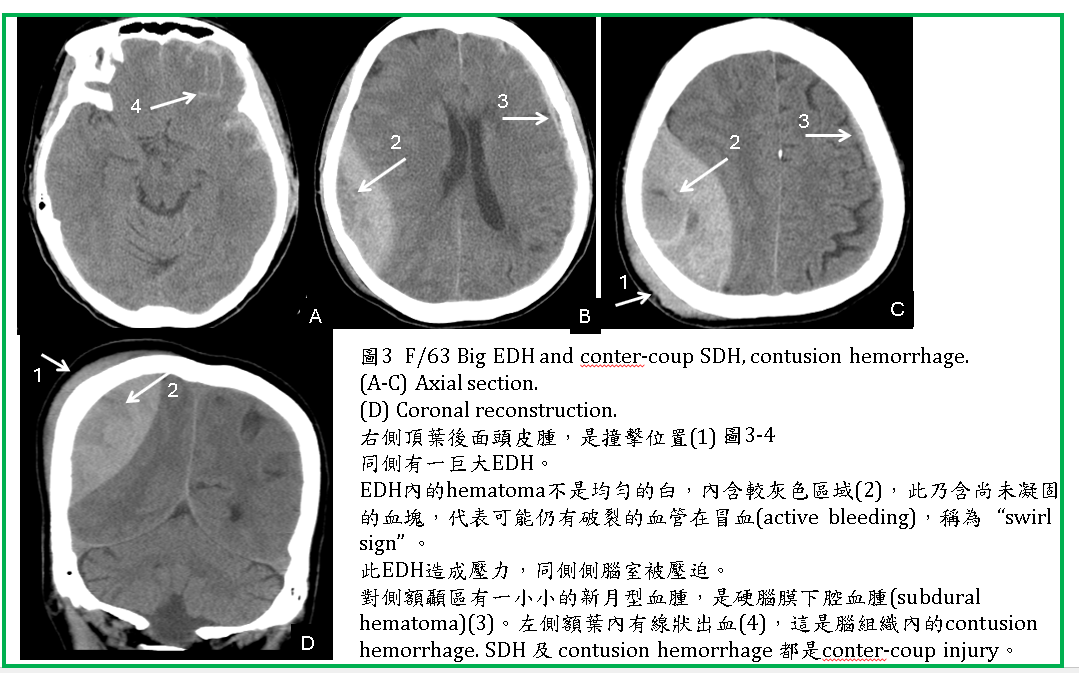

如果在做CT時,血腫內仍有動脈在出血,則血腫內含有未凝固的血液時,可在血腫內看到較灰或較暗的區域,使整個血腫看起來像漩渦狀(swirl sign) (圖2,3) 。

EDH通常位於顳、頂葉區,如在額區,可能跨過中線(如falx)到對側(圖4) 。如在後顱窩或枕區,有可能跨過小腦天幕,使小腦天幕上下都有EDH (圖5) 。

EDH可能單獨發生,也會合併腦挫傷、腦水腫、SAH、IVH等等。